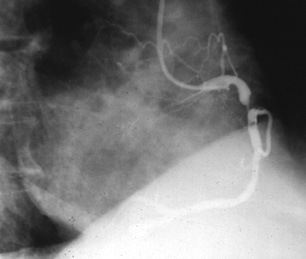

A coronary angiogram is performed.

Figure 1: Coronary angiogram

A representative section of his right coronary artery is shown: